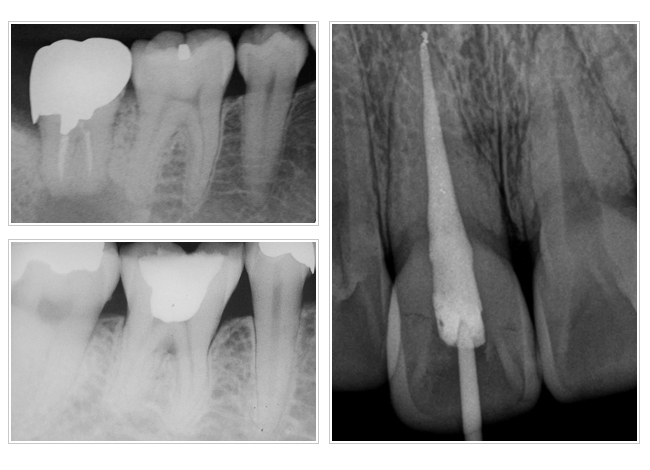

根管治療的步驟

一、蛀牙造成牙神經感染,骨頭遭破壞產生發炎反應。

二、根管治療將受細菌感染的牙神經去除,並將根管清潔擴大。

三、將已經滅菌的根管永久充填,您就可以安心做上假牙。

以上步驟都需戴橡皮障做治療,故好的根管治療可以讓已經遭破壞的骨頭再生,恢復牙根的健康。